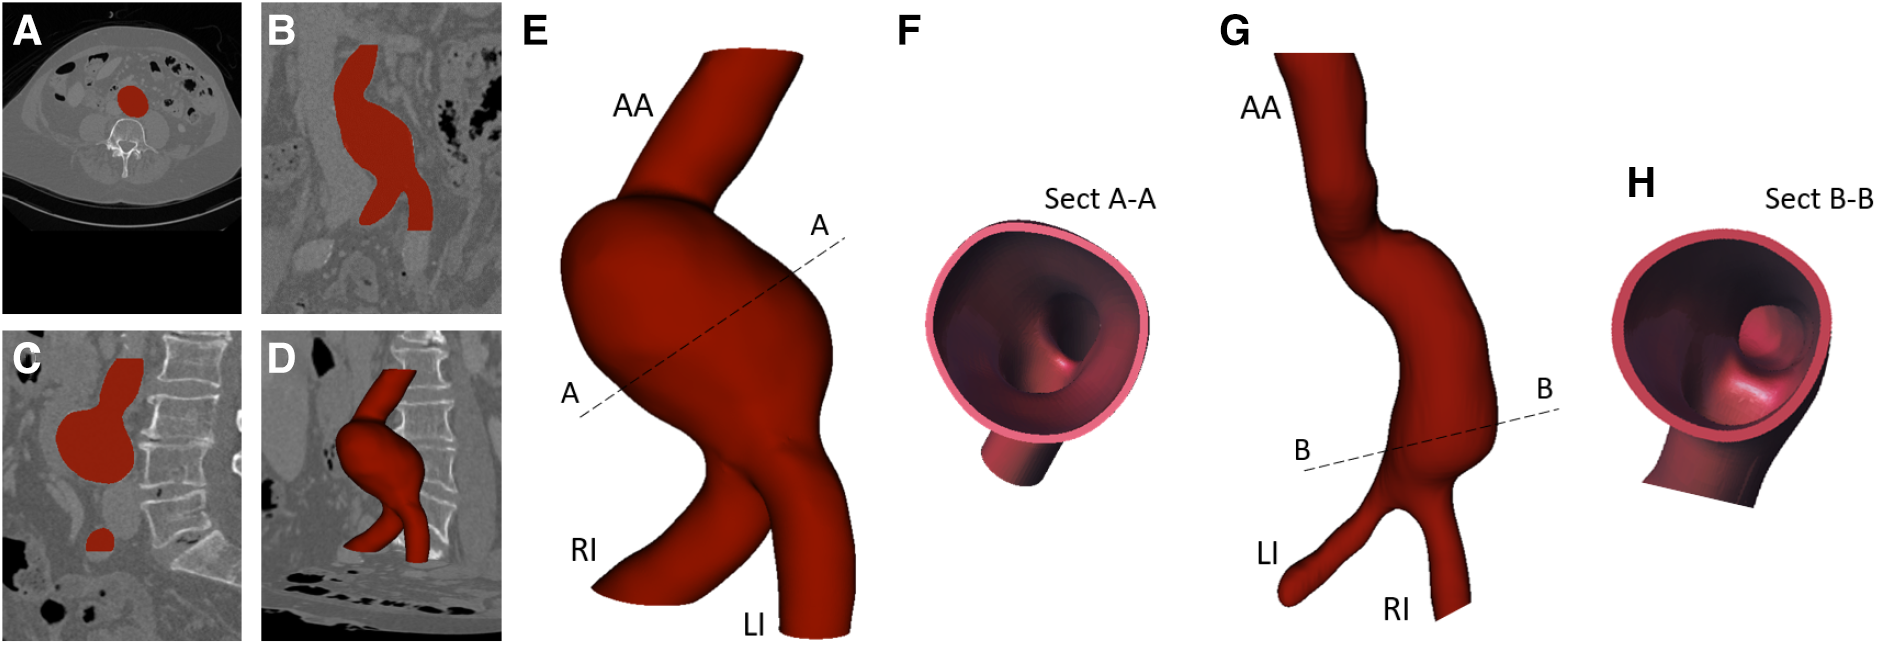

The images were segmented and the volume of the vessels was reconstructed with the open-source software 3DSLICER (Slicer, NIH) (50) by following the approach previously described in Celi et al. (51). Figures 1A–C show an example of segmentation in the axial, coronal, and longitudinal planes. The segmented AAA geometry is shown in Figure 1D.

Figure 1

Example of image segmentation in axial (A), coronal (B), longitudinal view (C), and segmentation result (D); 3D solid models (E, G) with related cross-sections (Sect) (F, H).

2.1.2. AAA solid model generation

The segmented geometries were exported as stereo-lithography format (stl) files and imported into the solid modeling computer-aided design (CAD) software SpaceClaim (ANSYS, Inc.) where the associated solid models were generated by means of non-uniform rational basis-splines interpolation. The 3D solid models are shown in Figures 1E,G. Both models include the abdominal aortic inlet (AA), aneurysm bulge, Left Iliac artery (LI), and Right Iliac artery (RI), which are the two outlets. The solid models were then imported into the CAD software SOLIDWORKS (Dassault Systèmes S. A., Vélizy-Villacoublay, France). Here, outward offset values of 1.8 and 2 mm were applied to the AAA models, respectively, to fix the thickness as shown by the cross-sections in Figures 1F,H.